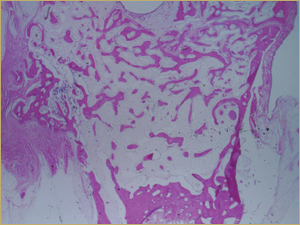

After 8 Weeks

By 8 weeks, all of the sinuses appeared histologically similar (Figs. 7–10). The mature lamellar bone that had been grafted in the autogenous bone group had been remodelled and was no longer present. Similarly, the numerous small-diameter woven bony trabeculae seen at 2 weeks in the BMP groups were no longer present. The sinuses all contained mature, small-diameter lamellar bony trabeculae. No qualitative histologic differences were apparent among the 5 treatment groups at 8 weeks (Figs. 7–10).

Figure 8: Low-power histologic examination of rabbit maxillary sinus augmented with demineralized bone matrix at 8 weeks after procedure. H&E stain, 100× magnification.